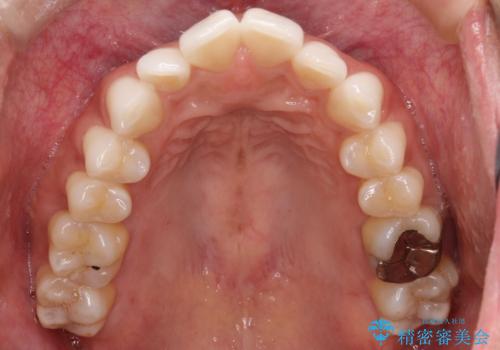

【インビザライン】前歯の凸凹をIPRで改善

- 前歯の凸凹を主訴に来院されました。

前歯を並べるために歯と歯の間にヤスリを入れてわずかに歯を削ることでスペースを確保しています。

歯と歯の間にヤスリを入れてわずかに歯を削ることでスペースを確保する処置をIPRと呼びます。

当院では拡大鏡を用いて丁寧に処置することで歯冠形態を損なわずに行うことができます。